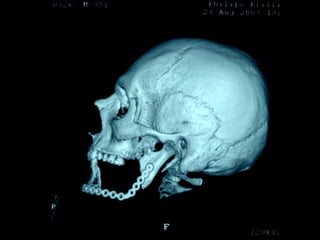

Trismus importante debido a que

El tumor ya rompió el hueso com-

Pacto de la cara interna de la

Mandíbula y empezó a tomar el

Músculo pterigoideo interno y

Sierra de GigliSierra de Gigli

Luxación de hemimandíbula

Pieza quirúrgica

Plantilla flexible para dar forma previa al implante

Se respetó el cóndilo para anclar la prótesisSe respetó el cóndilo para anclar la prótesis

Límite tumoralLímite tumoral

Area de lisis ósea a nivel de la línea

Miliodes que contracturó los músculos

Milohioideo y pterigoideo interno

Dificultando la deglución y determinando

Trismus importante.